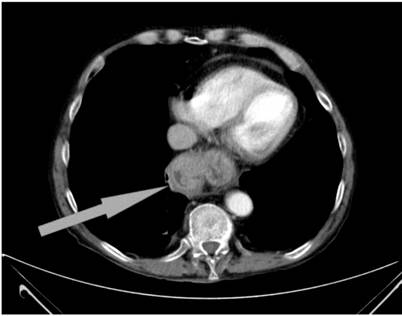

En la exploración llamaba la atención la delgadez del paciente, siendo el resto de la exploración física anodina. El análisis de urgencias mostró leucocitosis, trombocitosis, anemia ferropénica e hipoalbuminemia. Ante la sospecha de patología tumoral se le realizó una tomografía axial computarizada (TAC) abdominal que objetivó un engrosamiento parietal y captación de contraste a nivel de la unión gastroesofágica, y quedó ingresado para completar el estudio.

Se trató con fluconazol intravenoso durante un total de 14 días y la clínica mejoró parcialmente luego de las primeras dosis, pero empeoró posteriormente. Por este motivo fue intervenido quirúrgicamente ante la obstrucción hiatal por acodamiento de la fundoplicatura previa (Figura 2). Se le realizó una reposición hiatal a los parámetros anatómicos y se procedió al desmontaje del Nissen previo.